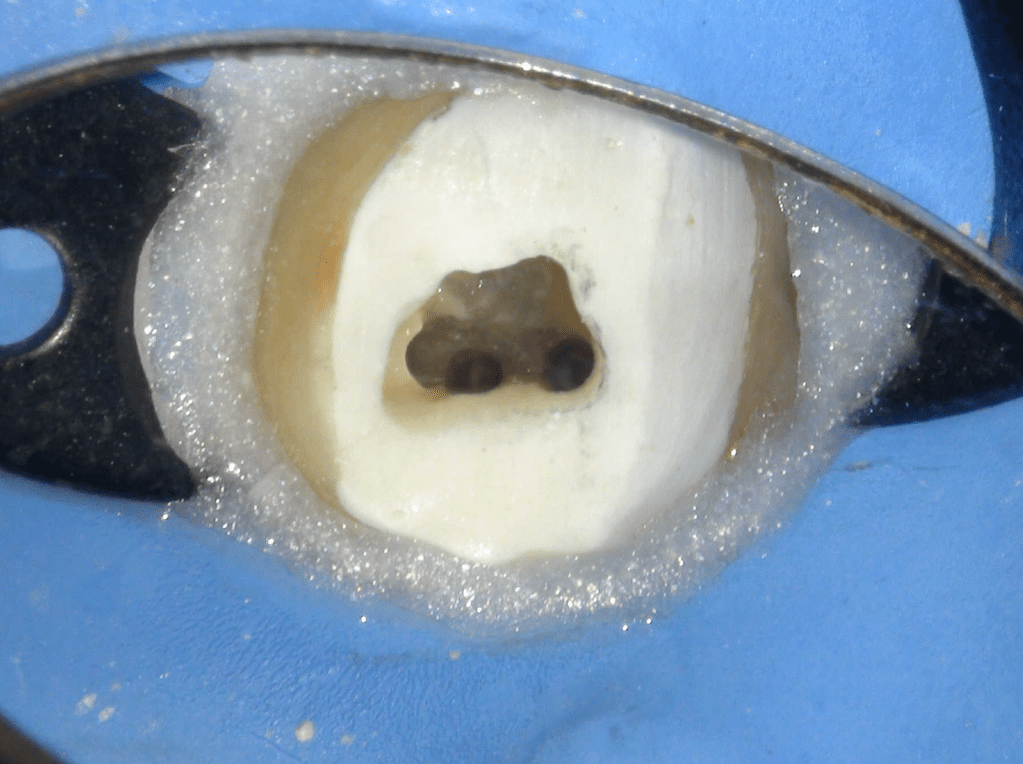

Pulpotomía biodentine + reco preendio